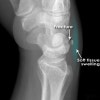

Avulsion chip fracture는 lateral, oblique view에서 잘 보입니다.

X-ray : 삼각골 골절(Triquetrum fracture)